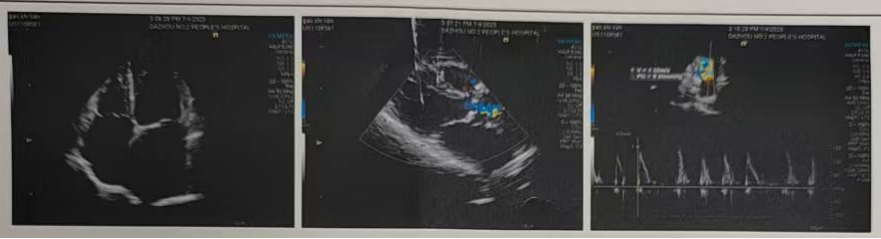

術(shù)后造影

術(shù)后超聲